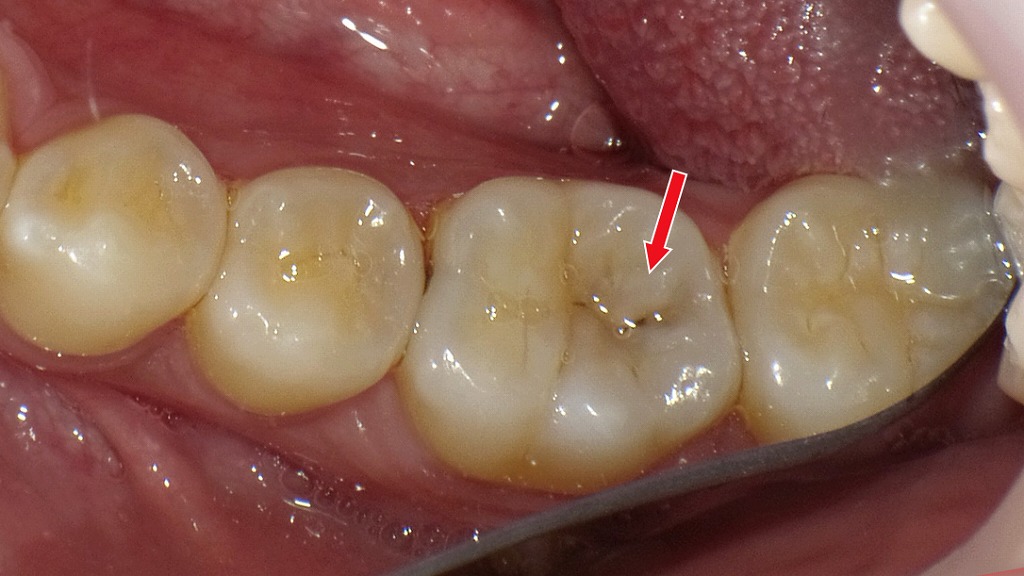

赤矢印が示すように、歯と歯の間(コンタクト部)の初期虫歯は、肉眼ではほとんど確認できません。レントゲンを撮影することで、エナメル質内部の透過像として虫歯を早期に発見できます。見た目に穴がなくても進行している場合があるため、定期的なレントゲン検査は非常に有効です。